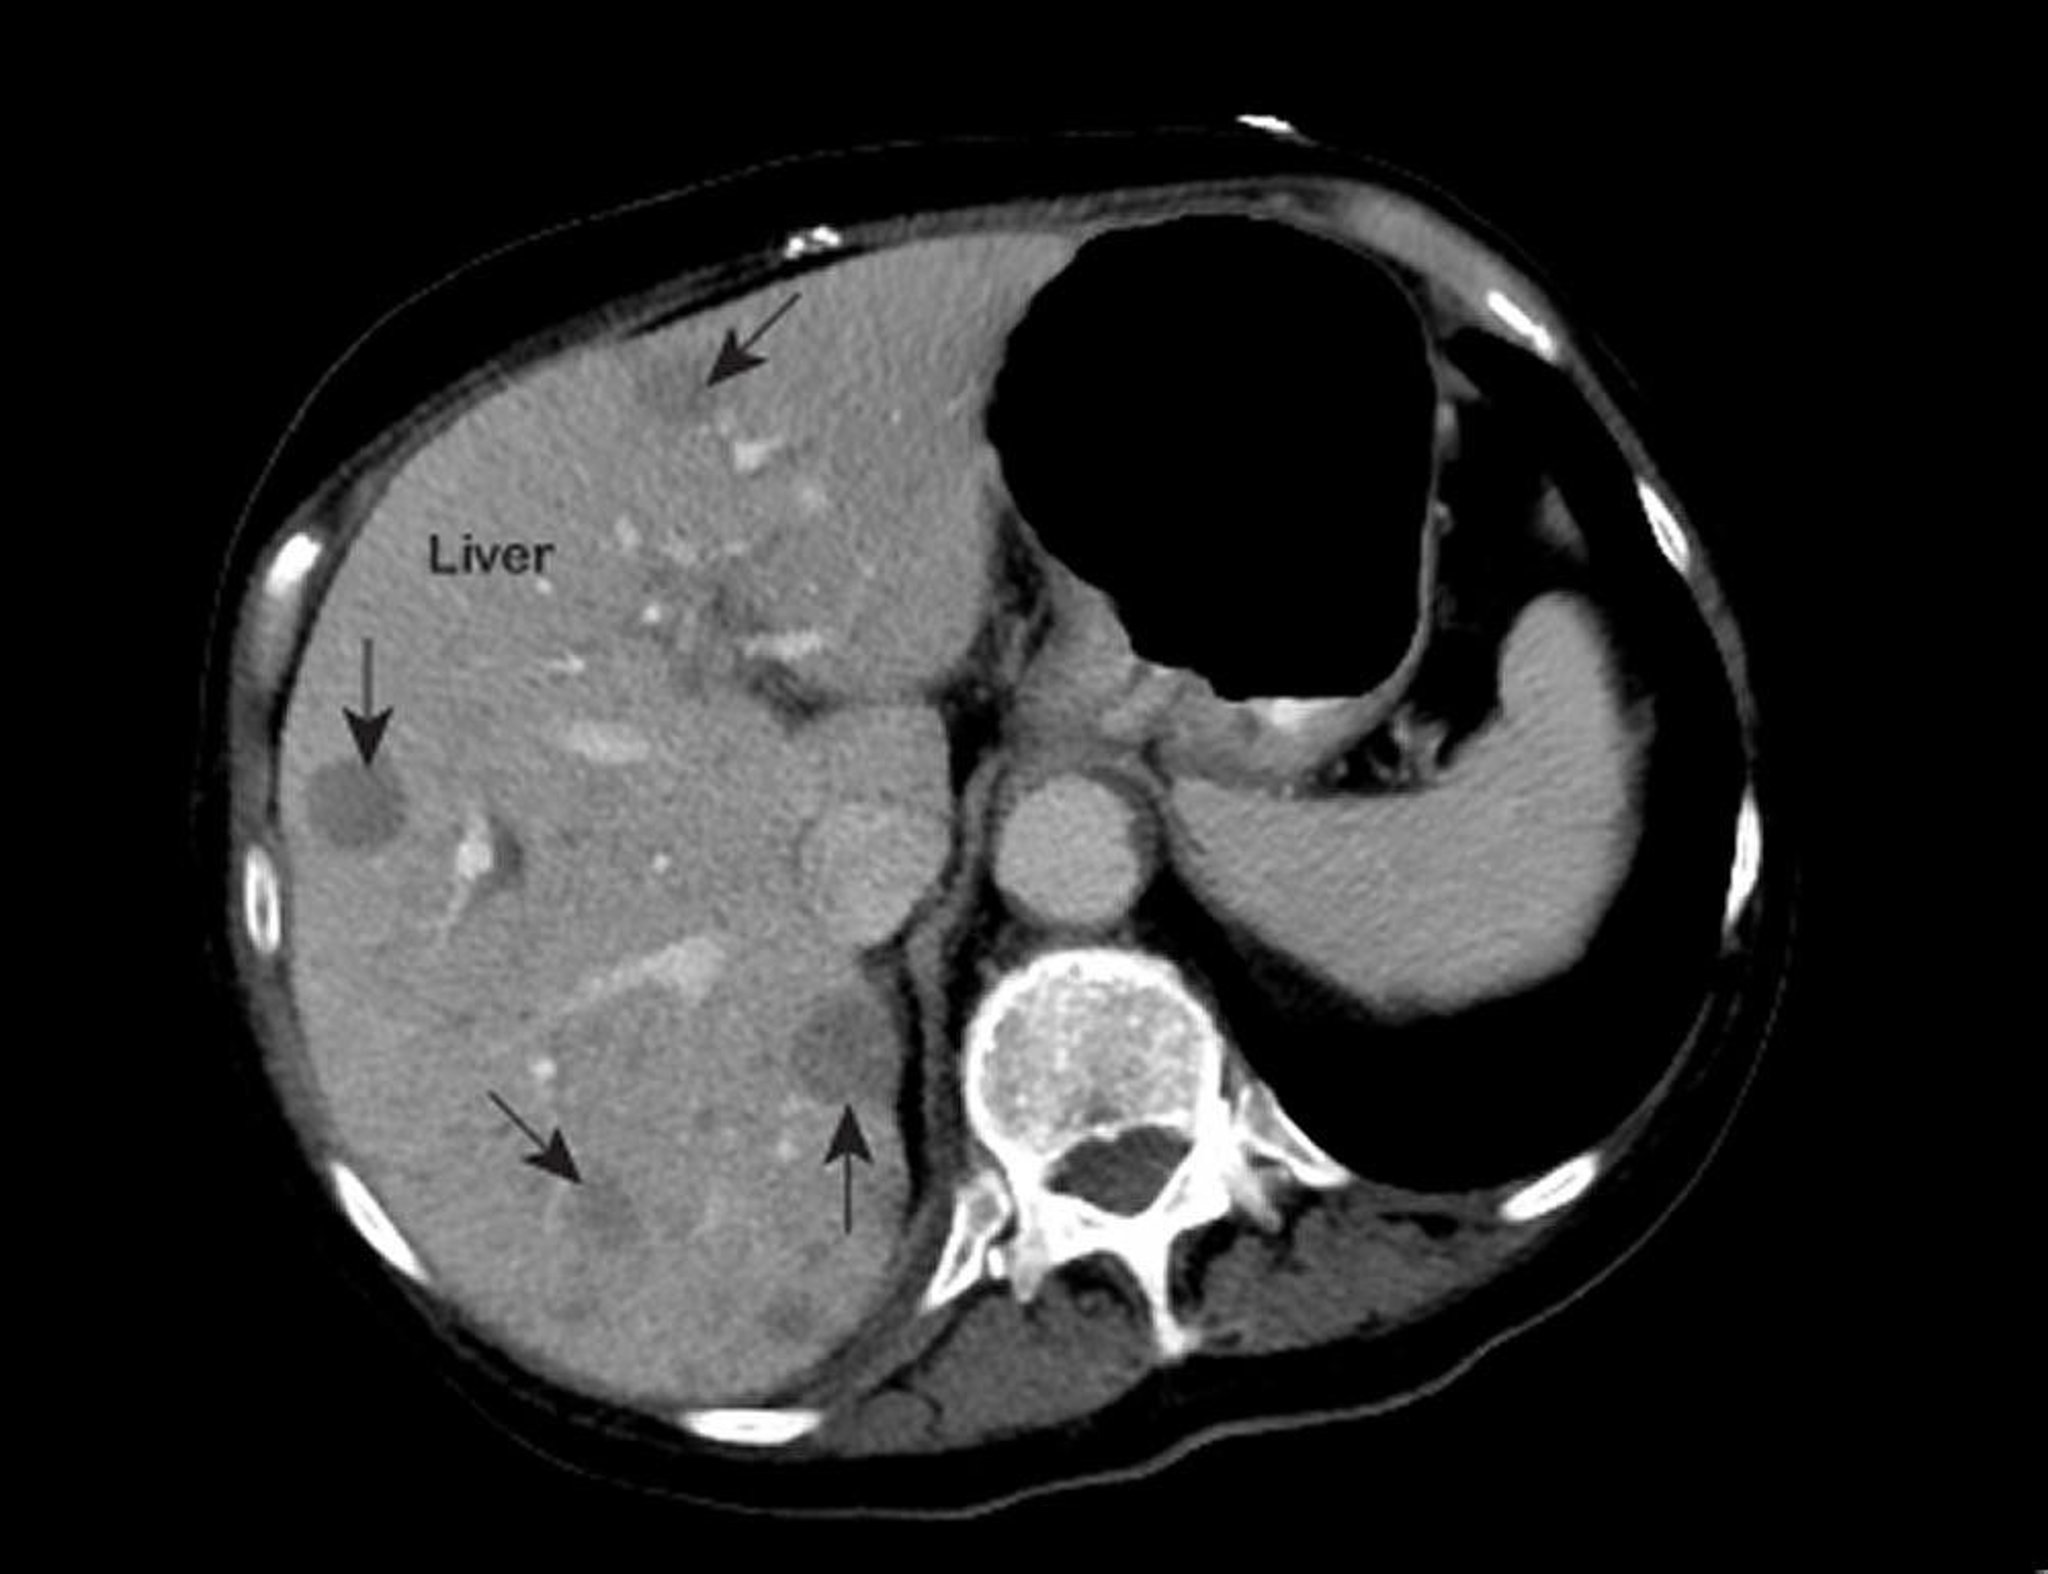

An abnormal MRI of the chest shows areas of low attenuation (marked with arrows) inside the liver. This appearance is typical of metastatic liver cancer.

Photo courtesy of Patrick O’Kane, MD.